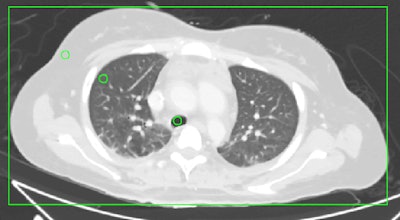

Image examples of regions of interest used for the quantitative evaluation in the thorax at the height of the tracheal bifurcation (above), the upper abdomen at the height of the portal vein (below, left), and the lower abdomen at the level of the lumbar spine L4 (below, right). A rectangle was used for measurements of the lateral and anterior-posterior diameter of the torso. Images courtesy of European Radiology.Conventional CT acquires images in a single broad energy band, but spectral CT separates energy into two or more narrow energy bands. Because different types of energies are absorbed differently by tissues, they can provide insights into the different chemical compositions of tissues.